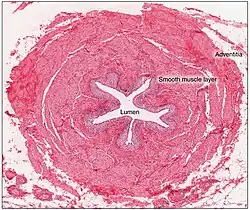

The ureter is lined by urothelium, a type of transitional epithelium that is capable of responding to stretches in the ureters. The transitional epithelium may appear as a layer of column-shaped cells when relaxed, and of flatter cells when distended. Below the epithelium sits the lamina propria. The lamina propria is made up of loose connective tissue with many elastic fibers interspersed with blood vessels, veins and lymphatics. The ureter is surrounded by two muscular layers, an inner longitudinal layer of muscle, and an outer circular or spiral layer of muscle.[6][7] The lower third of the ureter has a third muscular layer.[7] Beyond these layers sits an adventitia containing blood vessels, lymphatic vessels, and veins.[7]